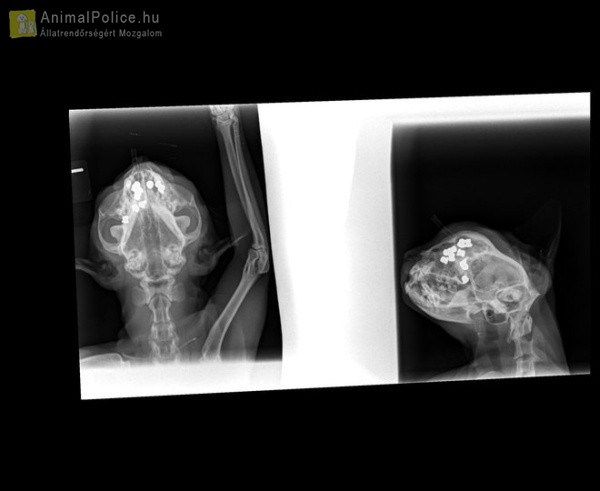

Csodával határos módon maradt életben Cirmi, miután egy ismeretlen kilencszer, közvetlen közelről fejbe lőtte. A kóbor cicát befogadói vitték el állatorvoshoz. Többórás műtéttel mentették meg a macska életét. Gennyedző, sebes fejjel vitték gazdái az állatorvoshoz Cirmit, a befogadott taszári kóbor cicát. Az állat rossz állapotban volt. A röntgenfelvételek láttán nem csak a gazdik, az orvosok is elborzadtak. Egyben és darabokban vették ki a golyókat. Érzékeny és nehezen feltárható helyen voltak a sörétek.

– Kilenc sörét volt a homloküregében, a szeme mögött és az orrüregében is. Az állat legalább fél évig járhatott a lövedékekkel, mivel némelyik már be volt tokosodva. Az is jól látszott, hogy valaki közvetlen közelről, szándékosan lőtte meg. Csoda, hogy egyáltalán túlélte. Így kóborolt az utcán – mondta a Cirmit kezelő állatorvos. A hároméves vörös cicát néhány hónapja fogadták be taszári gazdái. Észrevették, hogy a feje állandóan sebesedik. Nem volt más megoldás, mint egy kockázatos, több órás operáció. Cirmi infúziót és altatót is kapott.

Cirmi állapota már stabil, szerencsére a lövedékek nem értek létfontosságú szerveket. Idővel teljesen felépül majd.